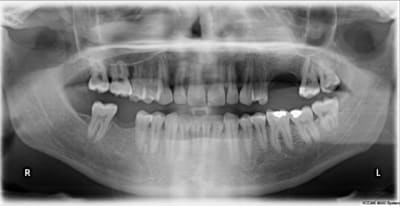

Patient 26 ans, à qui il manque 46, 25 et 26.

Pour l'instant je vous propose la partie préparation et mise en place de l'implant en 46, la suite peut être bientôt.

Dans l'ordre si le site veut bien, wax-up ( cirage pour céramik ;) ) , guide radio, et scan.

Photos pré-op, indicateur de direction en place et post-op.

Il s'agit d'un implant astra osseospeed de 5 mm de diamètre et 9 de long.

Prothèse prévue à 6 semaines.